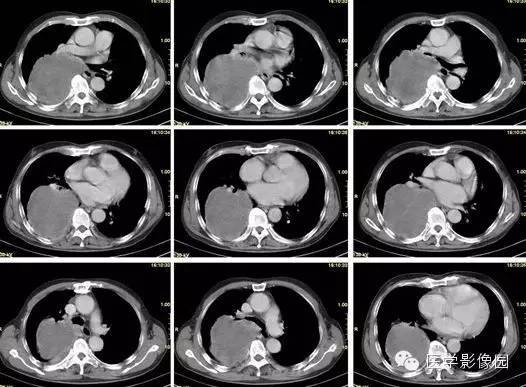

纵隔占位?肺内占位?巨大中央型肺癌1例

【病例】巨大中央型肺癌1例